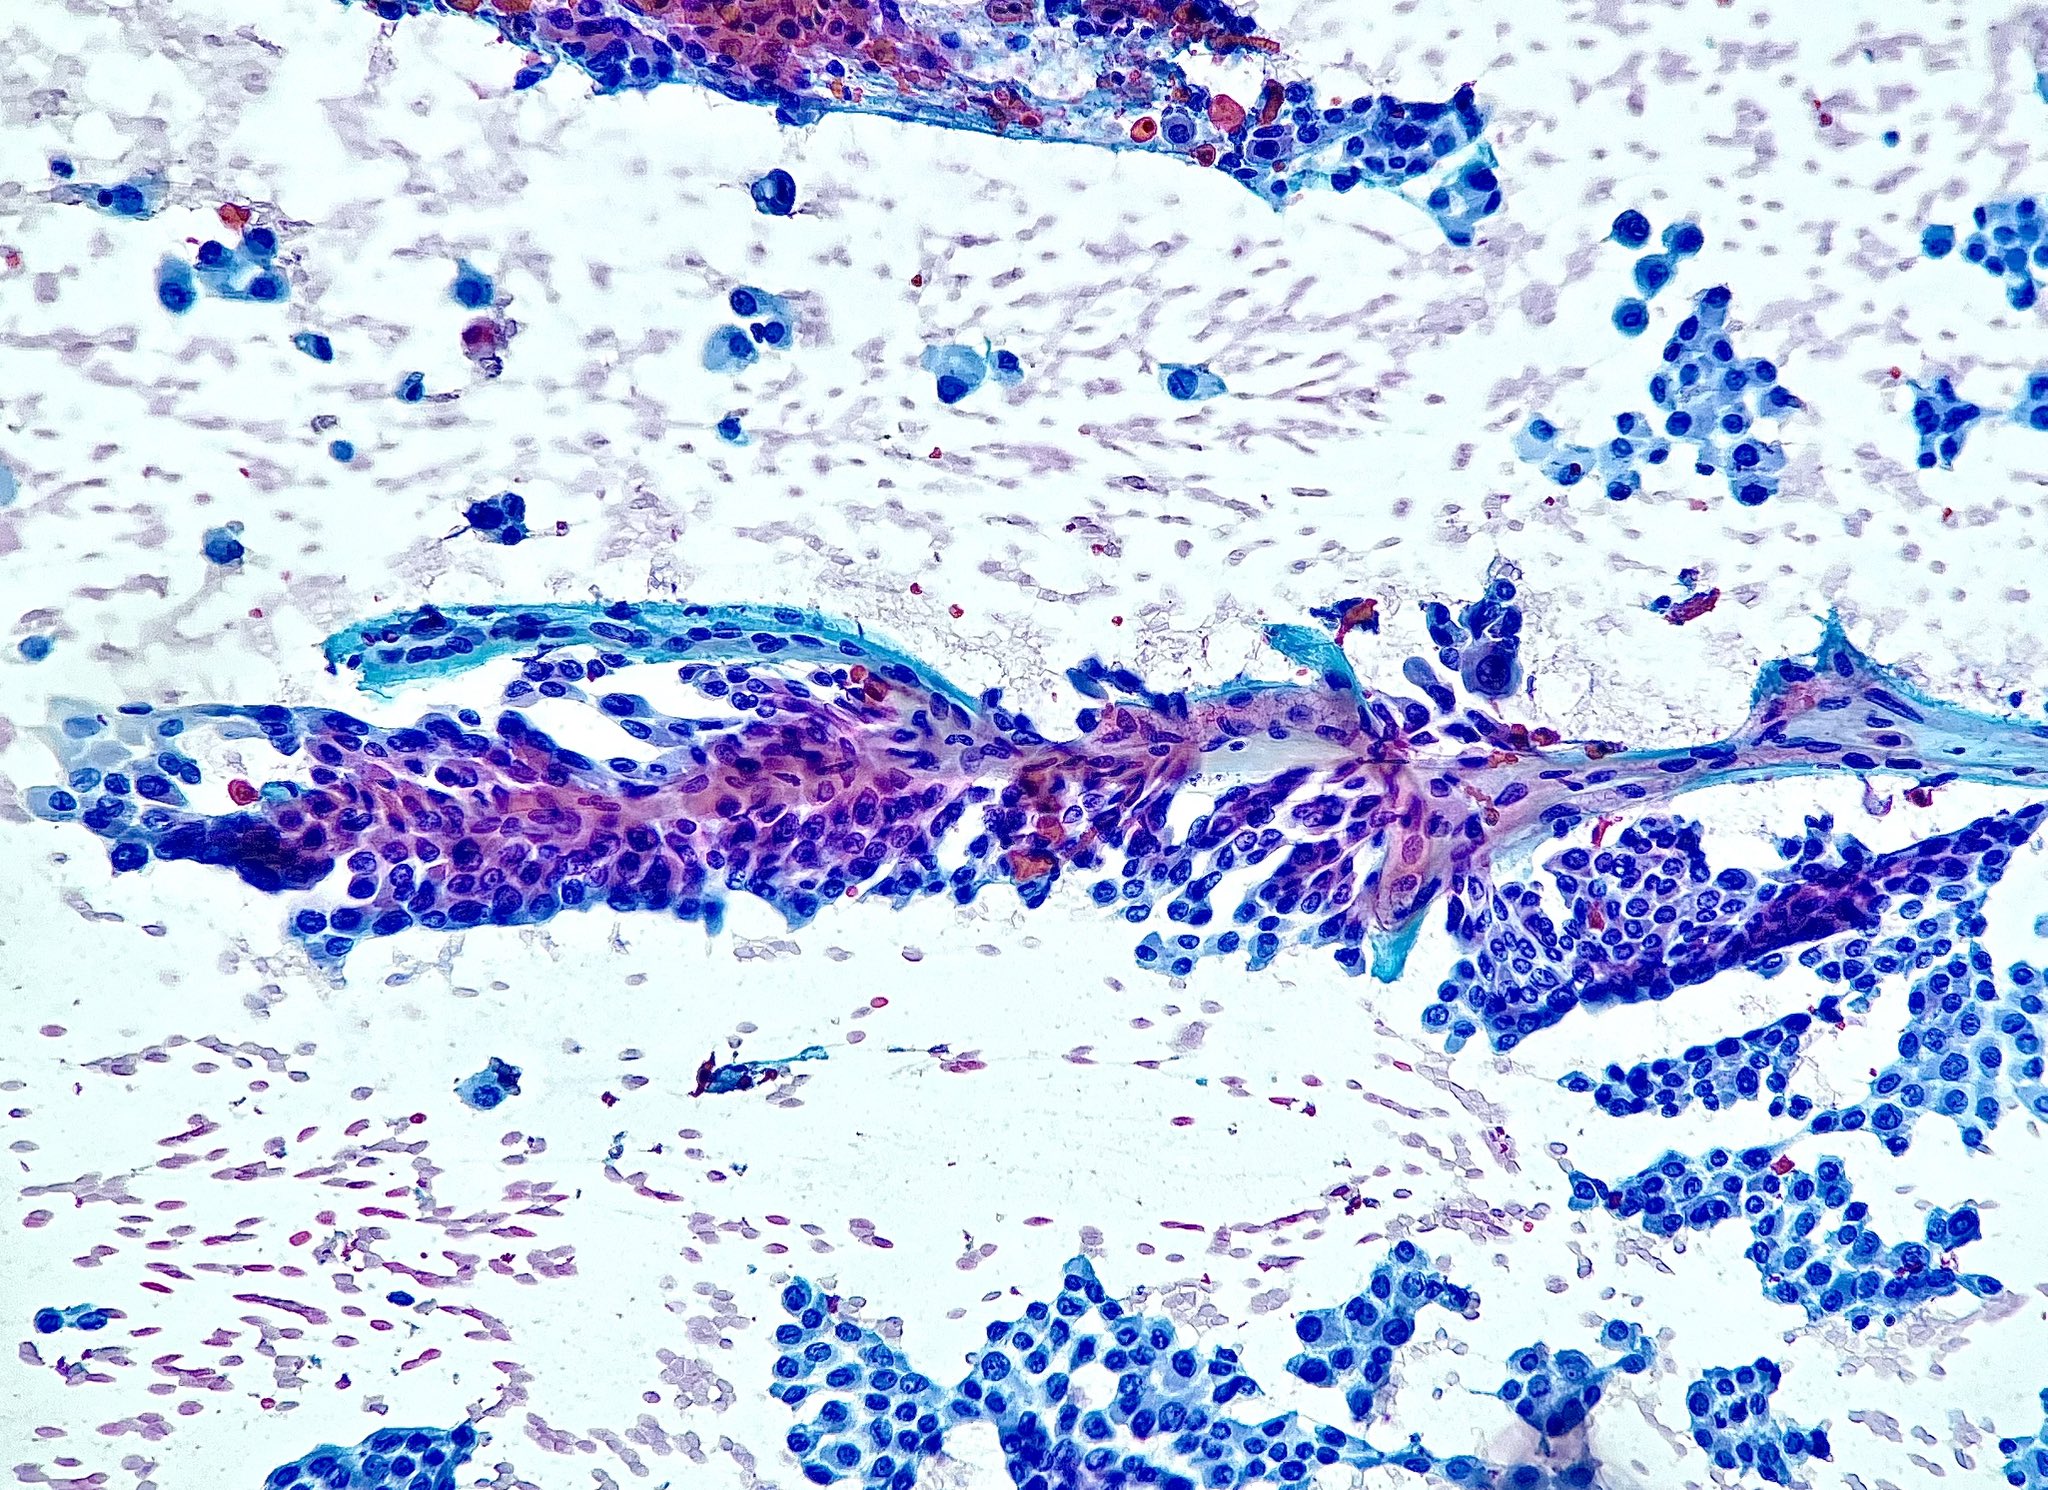

#PathX #PathTwitter #breastpath #USCAP2020w